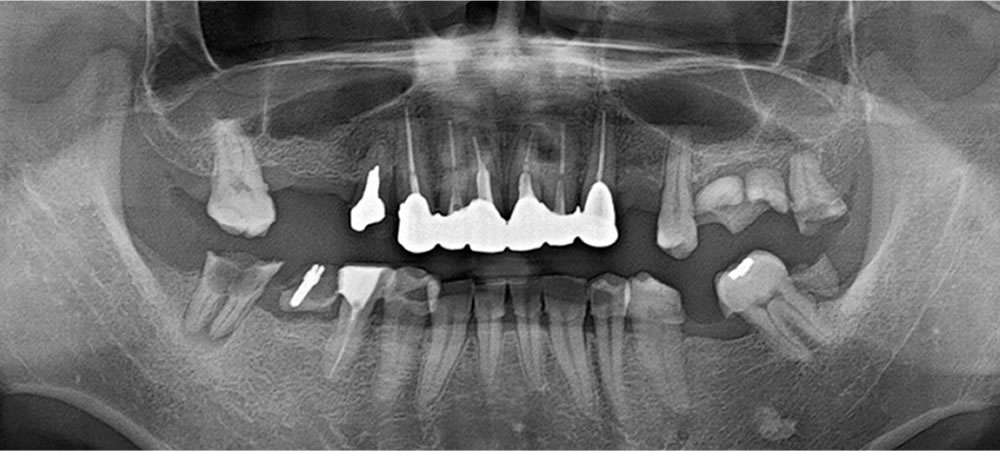

抜歯後の口腔内写真

抜歯後の口腔内写真です。歯茎は赤く腫れ上がり、歯石も帯状に付着しています。歯周病治療が必要な状態です。

患者様の主訴である「しっかりと噛めない」の原因は、噛み合わせに原因がありました。現在、患者様は下顎を前方に出して、無理やり歯同士が合わさるところで噛んでいたのです。中心位と呼ばれる下顎位に誘導すると、下顎が偏位し、歯同士が合わさりません。

患者様の主訴である「しっかりと噛めない」の原因は、噛み合わせに原因がありました。現在、患者様は下顎を前方に出して、無理やり歯同士が合わさるところで噛んでいたのです。中心位と呼ばれる下顎位に誘導すると、下顎が偏位し、歯同士が合わさりません。